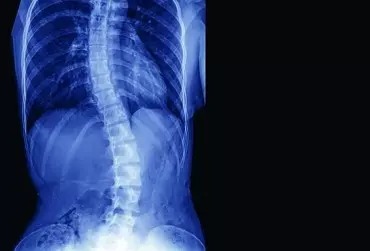

Promieniowanie RTG w praktyce fizjoterapeutycznej

Promieniowanie radiologiczne (RTG) jest złotym standardem diagnostyki obrazowej. Jest badaniem szybkim w wykonaniu, powszechnym i niedrogim, a ukazanie rzeczywistego obrazu układu kostnego daje mu atut, którym przewyższa nowoczesne badania diagnostyczne. Zastosowanie zarówno aparatów rentgenowskich, jak i innych diagnostycznych aparatów nieinwazyjnych ma swoje zasady, cele i wzajemnie się uzupełnia. Należy pamiętać, w jakich sytuacjach ich używać, aby wykluczyć czynnik szkodliwości w dojściu do celu, jakim jest diagnostyka pacjenta.